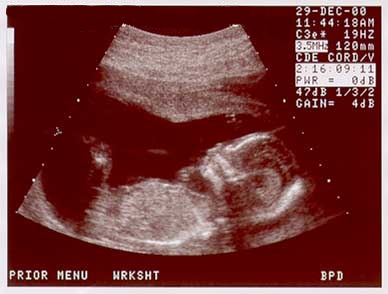

These images show the baby at 17wks. (Dec. 29, 2000) |

![]() Baby at 17 weeks, Image sequence 3 of 3 |